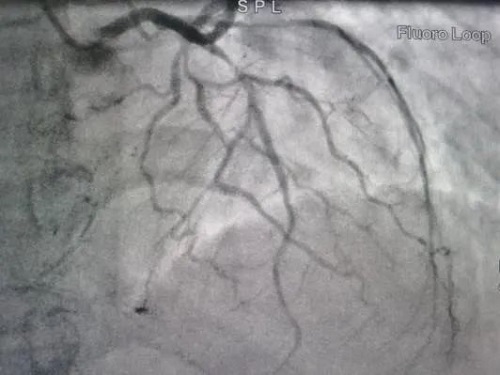

患者龙某,女,59岁,因胸痛2天加重2小时入院,2024年3月9日冠状动脉造影示左主干正常,前降支近中段长斑块,狭窄90%,TIMI血流3级,可见逆向血流至右冠远端;高位钝缘支可见散在斑块,狭窄80-90%,TIMI血流3级;右冠开口发出后完全闭塞,TIMI血流0级。

术前影像▼